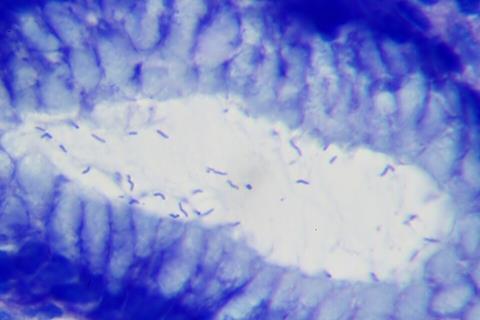

Gastric cancer often develops through a gradual sequence of changes, beginning with superficial gastritis and advancing through chronic atrophic gastritis, intestinal metaplasia, and precancerous lesions before culminating in malignancy. Helicobacter pylori infection, responsible for nearly 90% of non-cardia gastric cancers, plays a central role in triggering this cascade.

The investigation analyzed gastric tissue samples from 166 individuals in Linqu, a high-risk region in China, and 99 patients in Beijing, profiling over 4,200 proteins. From this dataset, 28 proteins were validated as key markers of H. pylori infection and gastric cancer, including up-regulated proteins such as OLFM4 and ENO1 and down-regulated proteins like GSN and IGFBP2.

Single-cell RNA sequencing of 135,000 gastric cells revealed that these protein-encoding genes exhibited stage-specific expression shifts during the transition from normal epithelium to intestinal metaplasia and ultimately malignant cells.